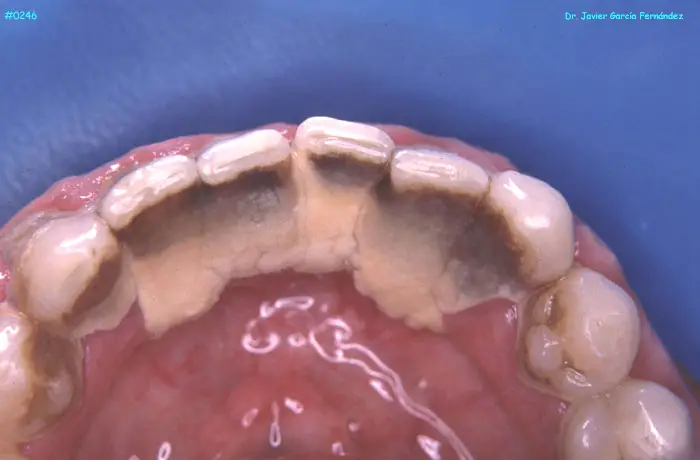

ATLAS DE CIRUGIA PERIODONTAL